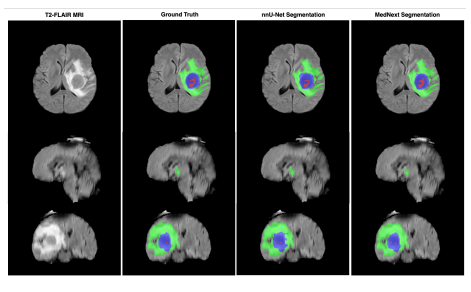

🧠 Brain Tumor Segmentation

Developed ensemble models for brain tumor segmentation on Sub-Saharan MRI data. Presented at MICCAI 2023 with scholarship award.

- MICCAI 2023 Scholarship recipient

- Novel Staple Assembling & Mednex methods

- Resource-limited healthcare focus

- Clinical application ready

Brain Tumor Segmentation on Sub-Saharan MRI

Ensemble methods for improved medical imaging segmentation on limited datasets. MICCAI Scholarship recipient.